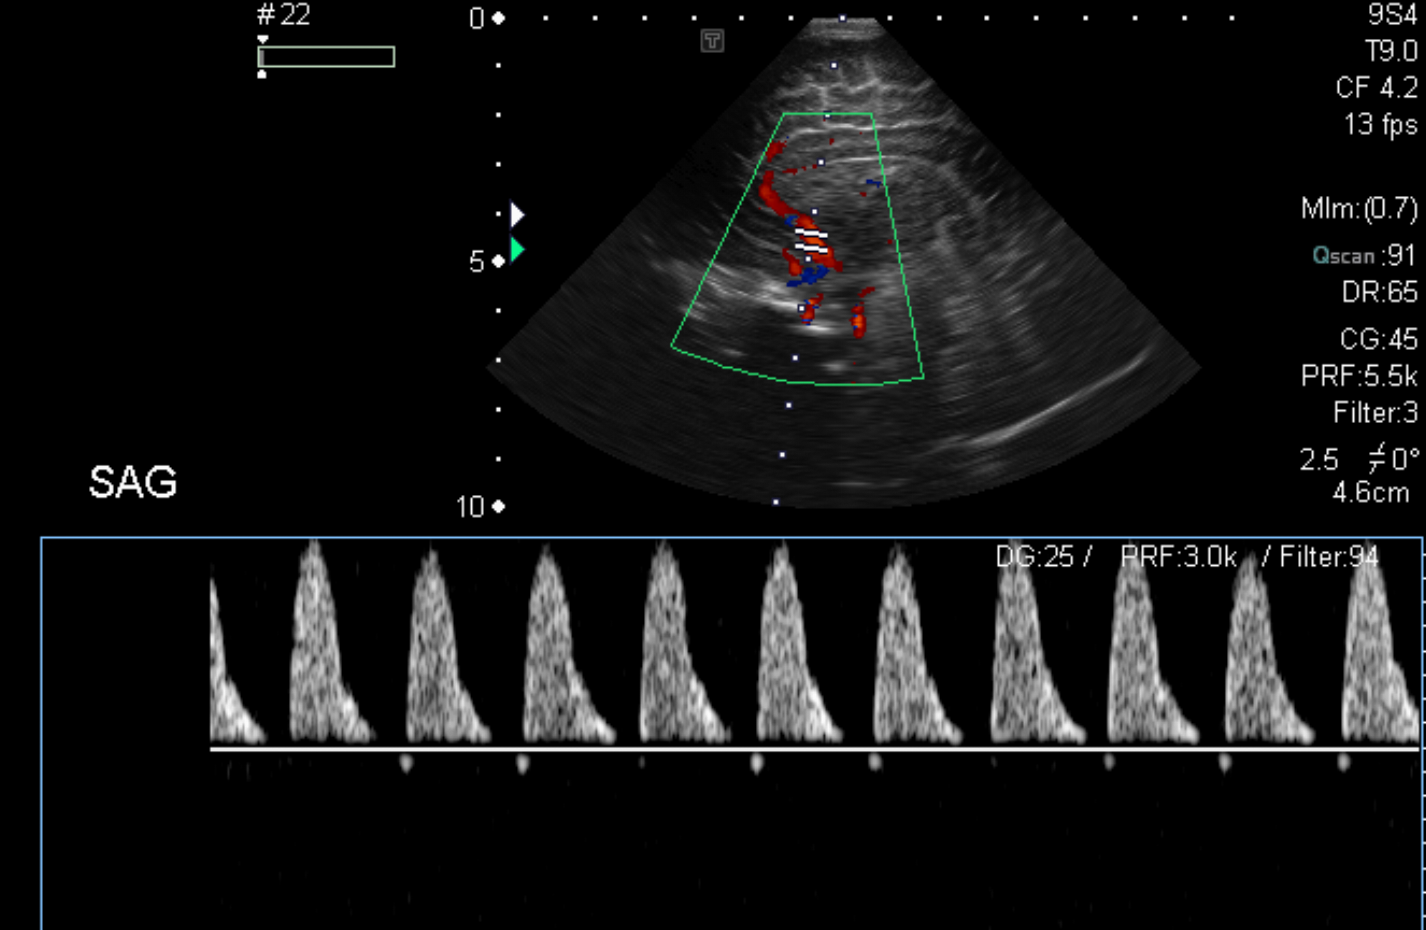

Section 1 Submit Findings Case149 Findings Brain The brain is immature. Yes No There is under-sulcation and open sylvian fissures. Yes No There is/are multiple hypoechoic areas in the periventricular white matter. Yes No There is/are multiple hyperechoic areas in the periventricular white matter. Yes No There is diffuse cerebral edema with diffusely increased echogenicity of the brain parenchyma and loss of grey white matter differentiation. Yes No The thalami/basal ganglia are hypoechoic. Yes No There is periventricular calcification. Yes No There is intra-parenchymal calcification. Yes No CSF spaces/ventricular system There is a prominence of the extra axial fluid spaces. Yes No There are debris/septations in the extra axial fluid spaces. Yes No There are debris/septations in the ventricles. Yes No There is a subdural collection on the right/left side. Yes No There is prominence of the ventricular system. Yes No There is an asymmetry of the ventricular system. Yes No There is a cavum septum pellucidum. Yes No There is a midline shift towards right/left. Yes No The choroid plexus is bulky/lobulated. Yes No There is a choroid plexus cyst measuring… Yes No There are debris/clots in the occipital horn. Yes No There is a posterior fossa cyst measuring… Yes No The tentorium is elevated/depressed. Yes No The lateral ventricle/s are dilated. Yes No The third ventricle is dilated. Yes No The 4th ventricle is dilated. Yes No There are pseudo cysts. Yes No Germinal matrix hemorrhage (Only in the premature infants): Please do not answer if the patient is a full term. There is a germinal matrix hemorrhage, consistent with a grade I hemorrhage. Yes No There is an intraventricular extension consistent with a grade II hemorrhage. Yes No There is an intraventricular extension with the dilatation of ventricles, consistent with a grade III hemorrhage. Yes No There is an intra-parenchymal extension, consistent with grade IV hemorrhage. Yes No On color Doppler examination, the Resistive index in the anterior cerebral artery is… There is a loss of the diastolic flow on the Doppler exam. Yes No There is altered vascularity on Doppler imaging. Yes No There is an AVM in the region of… Yes No